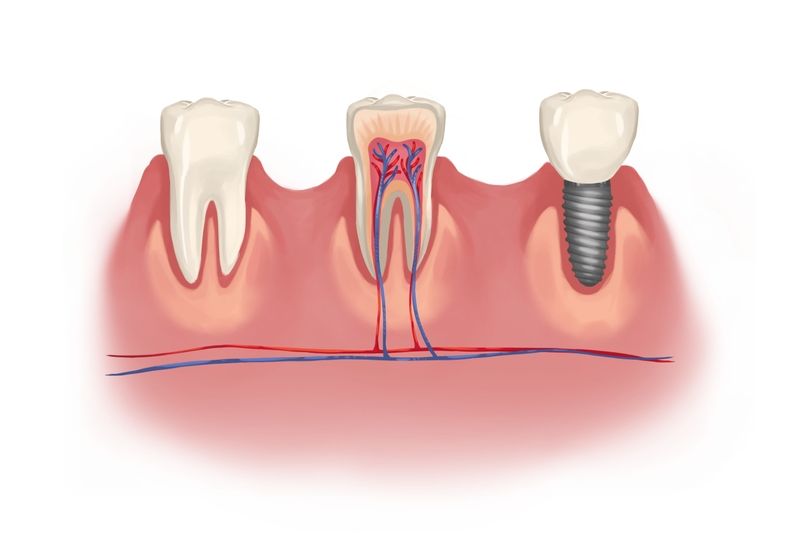

Dental implants are artificial tooth roots utilized to support the repair of a missing tooth or teeth, assisting to avoid or stop jaw bone loss. The implantation treatment is classified as a type of prosthetic (artificial replacement) dentistry however likewise is thought about a type of cosmetic dentistry.

Implants can be utilized to change a single tooth, a number of nearby teeth, all missing teeth in a jaw, or to support a set or detachable denture. The variety of implants being put will depend upon the last repair and the quantity of bone offered for the implant.